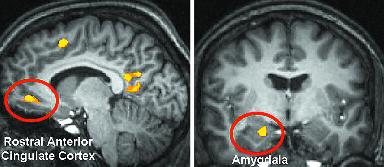

El cerebro feliz. Las zonas señaladas en rojo, la corteza cingulada anterior y la amígdala, aparecen con activación importante en la fMRI.